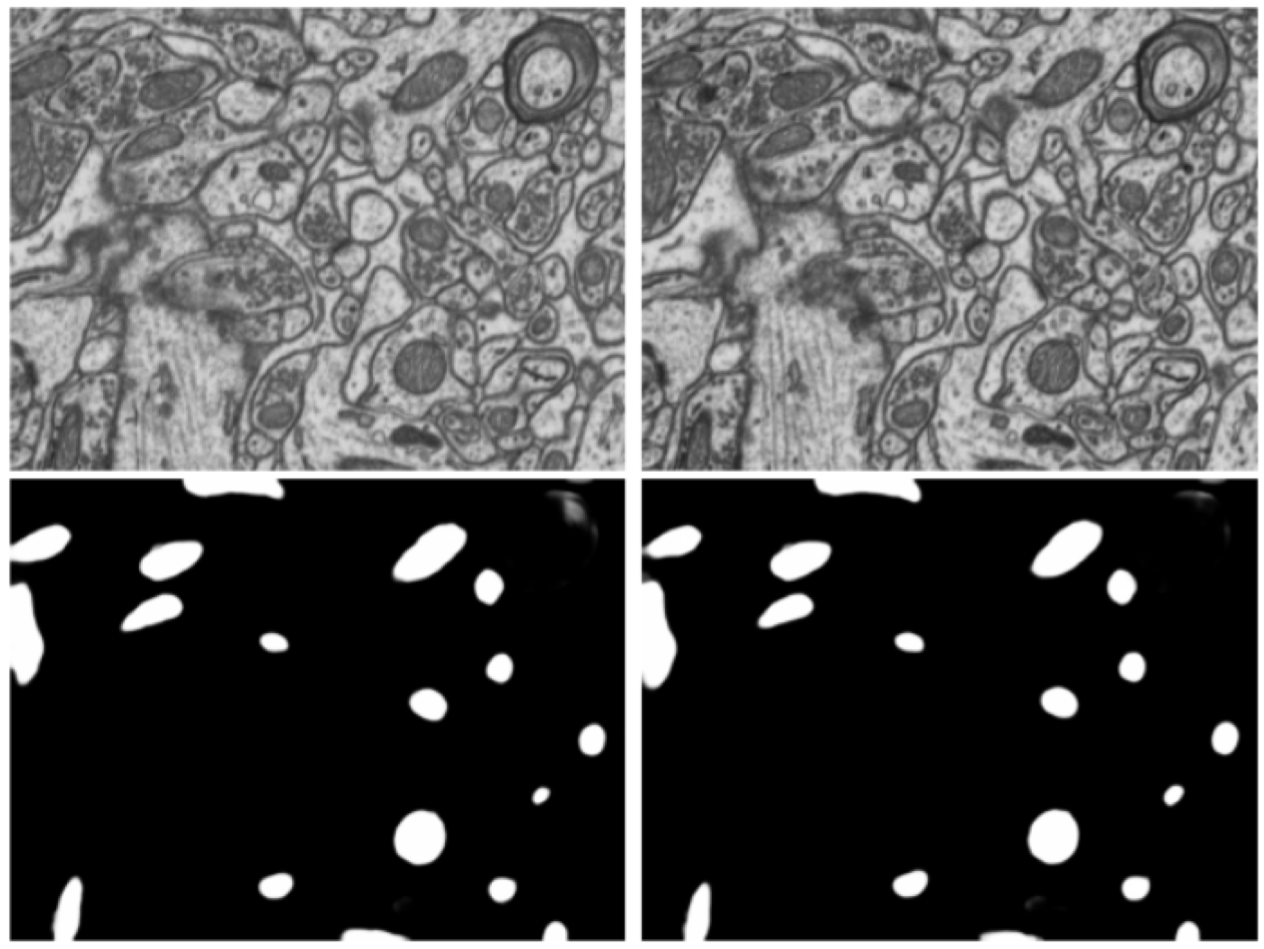

Results. Fig. 6 visualizes the raw model prediction without thresholding or median filtering on the EPFL Hippocampus test volume. In the quantitative comparison with previous state-of-the-art works on this dataset (Table 2), we show that our model surpasses human annotation performance provided by Casser et al. [6]. Besides, different from the best performing method [35] which has a complex post-processing step including watershed-based boundary refinement, we only apply a simple median filtering with a cubic kernel after model inference.

Dataset and Evaluation Metric. Besides semantic segmentation tasks, including synaptic cleft and mitochondria segmentation, we also work on the more challenging instance segmentation problem, which assigns each object a unique index. Specifically, we use the large-scale MitoEM dataset [51] for segmenting mitochondria instances, which is over larger than the Lucchi dataset [30] and has two volumes covering human (MitoEM-H) and rat (MitoEM-R) brain tissues, respectively. A difficult case for segmentation algorithms is demonstrated in Fig. 6. Both volumes are partitioned into consecutive train, val and test splits with 40%, 10% and 50% of the data. For evaluation, we use the 3D average precision (AP) metric with a mask IoU threshold of 0.75, denoted as AP-75. The test sets are automatically evaluated on the challenge website333IEEE-ISBI 2021 MitoEM challenge: https://mitoem.grand-challenge.org/.